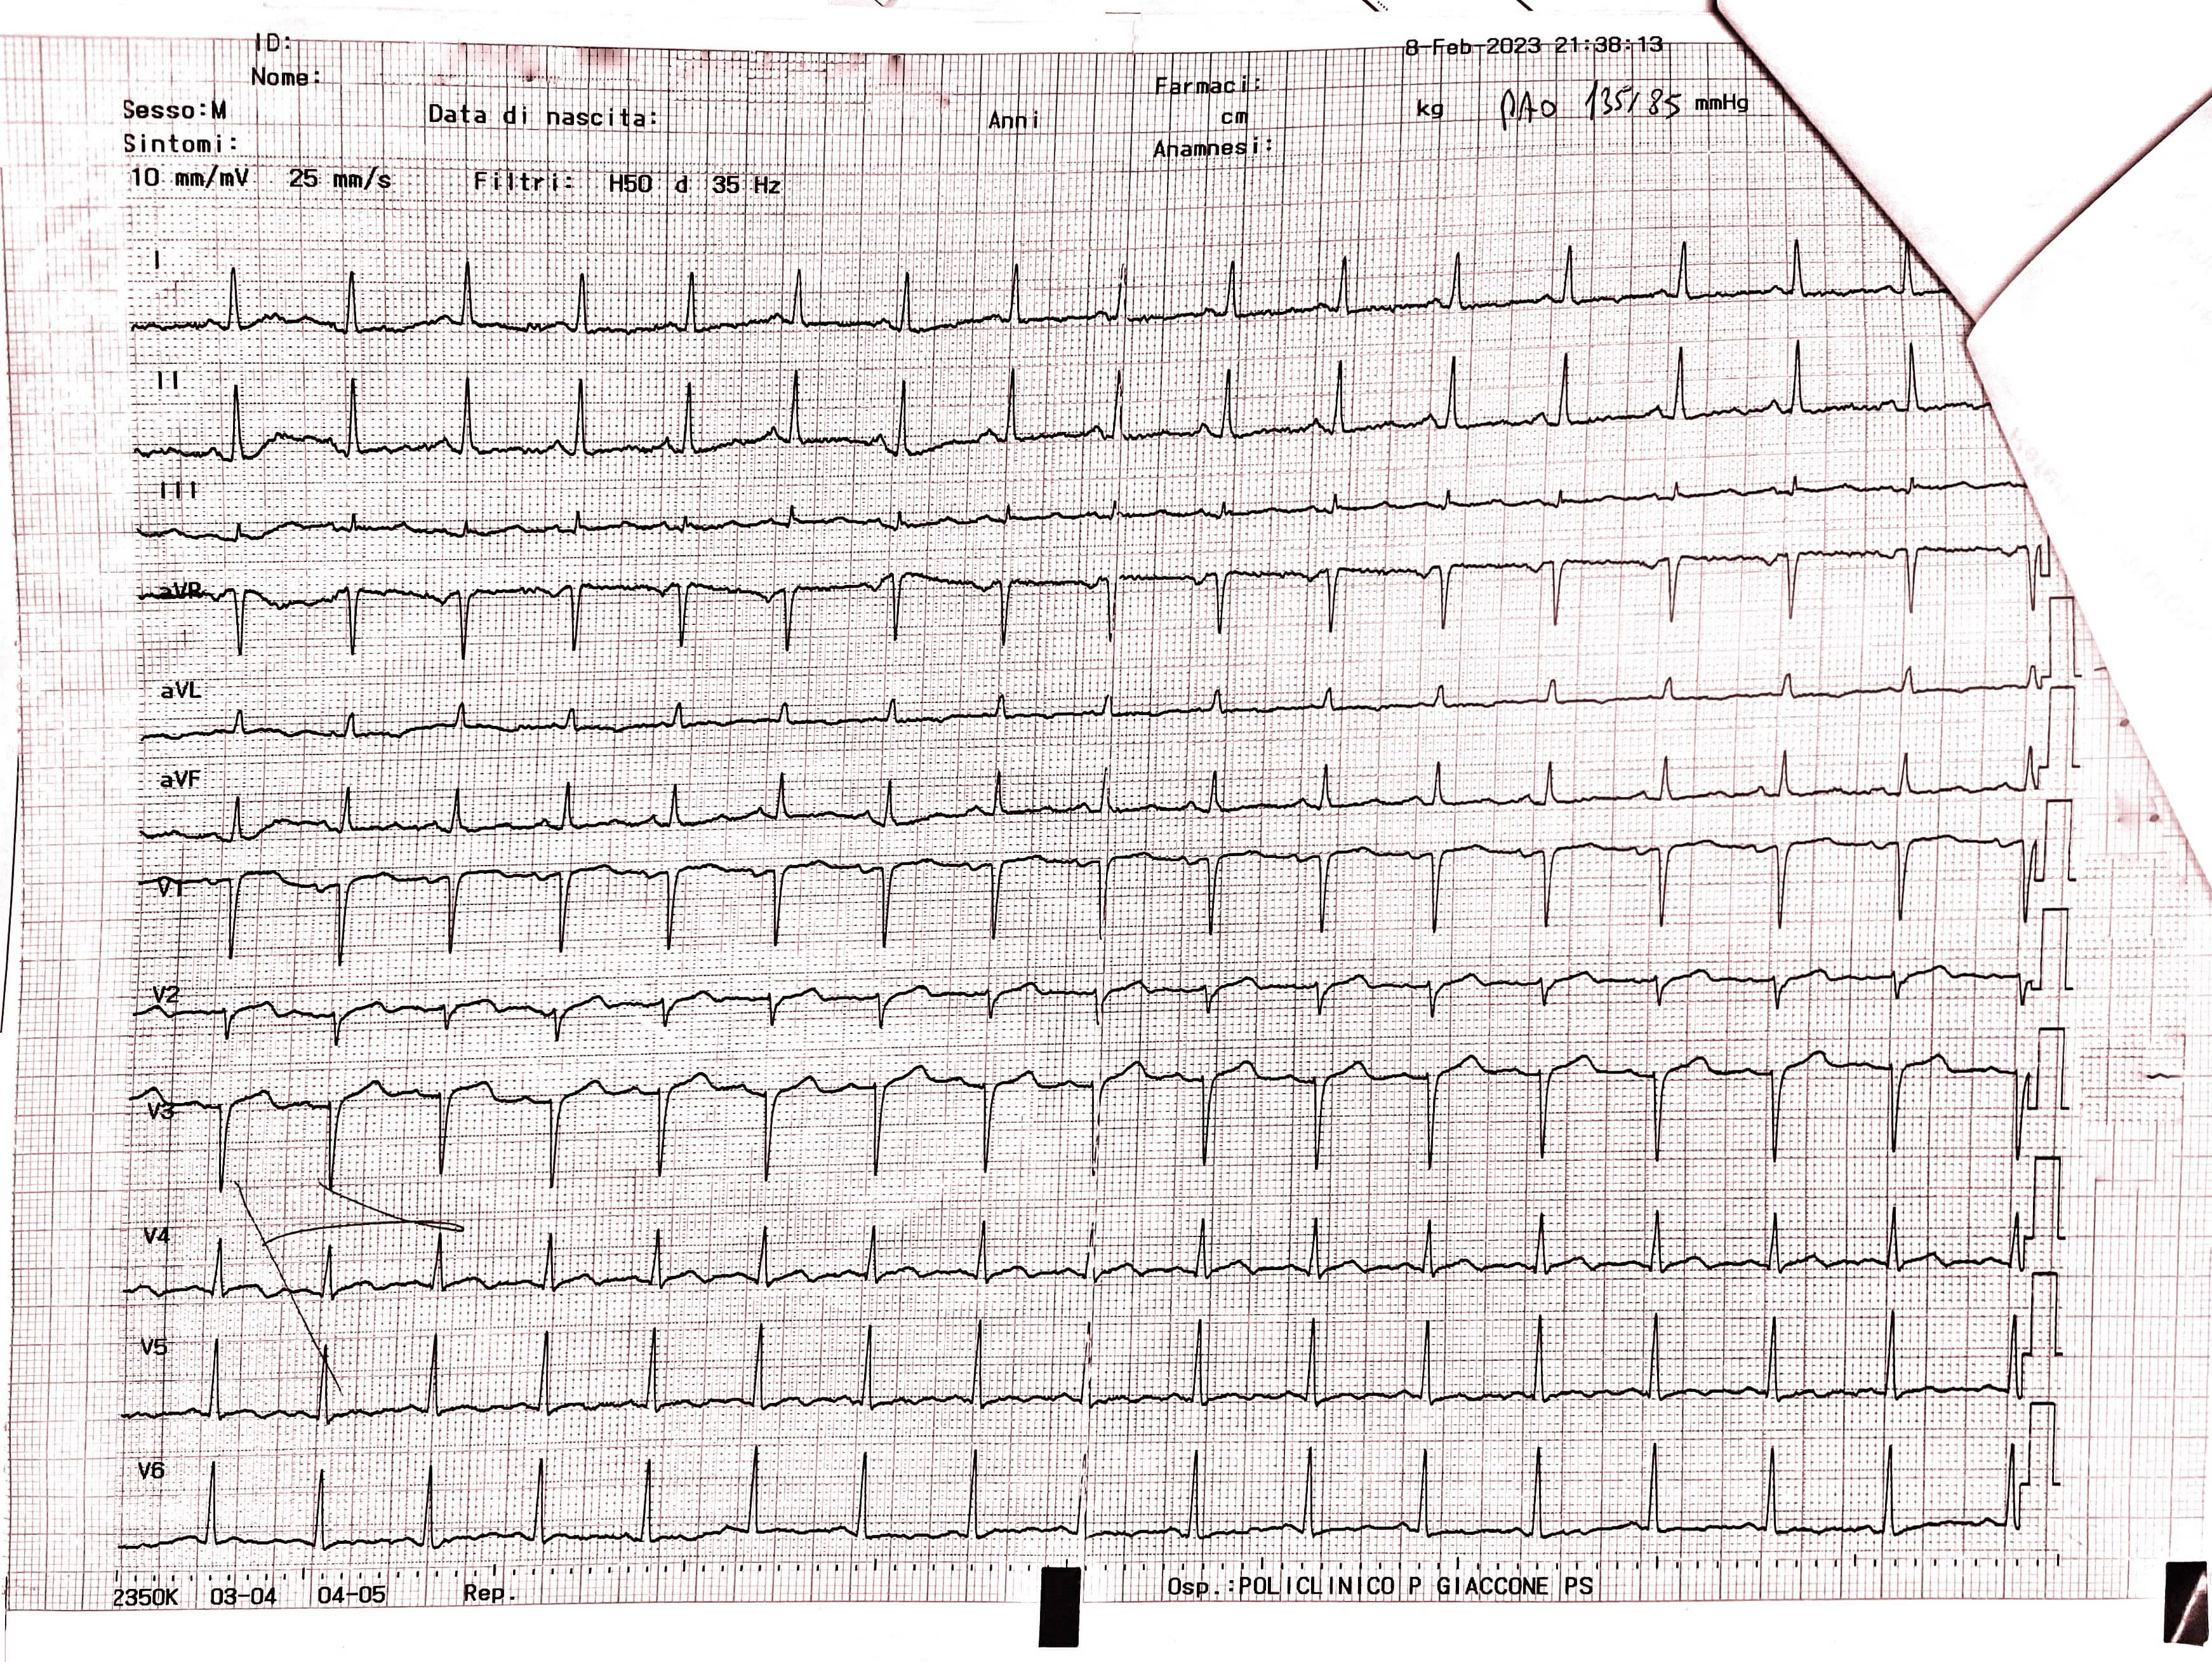

A bedside cardiac ultrasound was then performed, which showed evidence of akinesia in the apex and periapical segments, the mid anteroseptal segment, and the anterior wall, and hypokinesia in the mid anterolateral segment, leading to a mild decrease in overall systolic function (left ventricular ejection fraction [LVEF]: 43%). The left ventricle was slightly dilated with a minor increase in parietal thickness and a II degree diastolic dysfunction. Additionally, there was mild enlargement of the left atrium, mild-to-moderate mitral regurgitation, and mild tricuspid insufficiency with an estimated pulmonary arterial pressure systolic (PAPs) of 45 mmHg (Fig. 3).

Fig. 3.

Fig. 3.End-diastolic frame (Left) and End-systolic frame (Right) of the bedside cardiac ultrasound showing evidence of hypo-akinesia in the apex, periapical segments, mid anteroseptal segment and the anterior wall, leading to a mild decrease in overall systolic function (left ventricular ejection fraction [LVEF]: 43%).